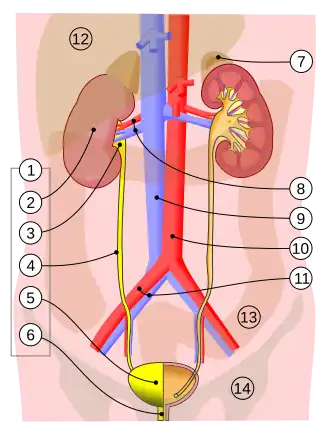

Estrutura

Os ureteres são estruturas tubulares, com aproximadamente 20-30 cm Em adultos humanos,[1] que passam da pelve de cada rim para a bexiga. Da pelve renal, eles descem em cima do músculo psoas maior para alcançar a borda da pelve. Aqui, eles se cruzam na frente das artérias ilíacas comuns. Em seguida, eles passam ao longo dos lados da pelve e, finalmente, curvam-se para a frente e entram na bexiga pelos lados esquerdo e direito na parte posterior da bexiga.[2] Os ureteres têm entre 1,5 a 6 mm de diâmetro[1] e são circundados por uma camada de músculo liso por 1 a 2 cm próximo às suas extremidades, pouco antes de entrarem na bexiga.[2]

Os ureteres entram na bexiga pela superfície posterior, viajando 1,5–2 cm antes de se abrirem na bexiga em um ângulo em sua superfície posterior externa nos orifícios uretéricos em forma de fenda.[2][3] Essa localização também é chamada de junção vesicoureteral.[4] Na bexiga contraída, eles estão separados por cerca de 25 mm e aproximadamente à mesma distância do orifício uretral interno; na bexiga distendida, essas medições podem ser aumentadas para cerca de 50 mm.[2]

Várias estruturas passam por cima, acima e ao redor dos ureteres em seu trajeto dos rins até a bexiga.[2] Em sua parte superior, o ureter viaja no músculo psoas maior e fica logo atrás do peritônio. À medida que desce pelo músculo, passa pelo nervo genitofemoral e. A veia cava inferior e a aorta abdominal situam-se na linha média dos ureteres direito e esquerdo, respectivamente.[2] Na parte inferior do abdome, o ureter direito fica atrás do mesentério inferior e do íleo terminal, e o ureter esquerdo fica atrás do jejuno e do cólon sigmóide.[2] Conforme os ureteres entram na pelve, eles são envolvidos por tecido conjuntivo e viajam para trás e para fora, passando na frente das artérias ilíacas internas e das veias ilíacas internas. Eles então viajam para dentro e para frente, cruzando as artérias umbilical, vesical inferior e retal média.[2] A partir daqui, nos homens, eles se cruzam sob os canais deferentes e na frente das vesículas seminais para entrar na bexiga perto do trígono.[2] Nas mulheres, os ureteres passam atrás dos ovários e, em seguida, passam na seção da linha média inferior do ligamento largo do útero. Por um curto período, as artérias uterinas viajam no topo por um curto período (2,5 cm). Eles então passam pelo colo do útero, viajando para dentro em direção à bexiga.[2]